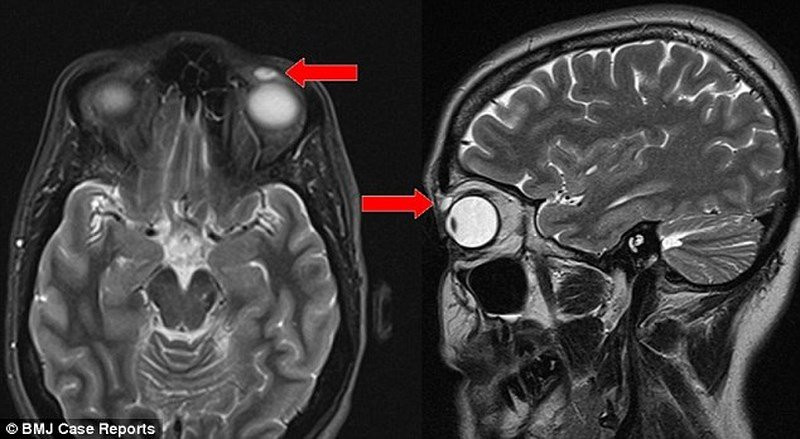

Phần kính áp tròng mắc kẹt trong mí mắt.

Cô bắt đầu cảm thấy khó chịu vì một vết sưng làm sụp mí trái. Sau nhiều tháng nhỏ thuốc không có hiệu quả, cô này tìm tới một trung tâm y tế uy tín để thực hiện các xét nghiệm. Các bác sỹ ban đầu cho rằng cục u nhỏ với kích thước 8mm x 4mm x 6mm là u nang và quyết định lấy bỏ nó ra khỏi mắt bệnh nhân.

Nhưng sau khi ca tiểu phẫu hoàn thành, họ mới phát hiện cục u đó thực chất là chiếc áp tròng dính vào mí mắt bệnh nhân cách đây 28 năm.